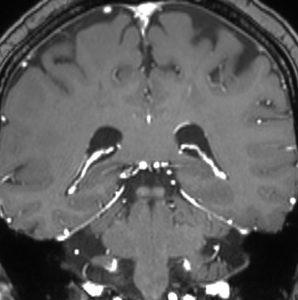

髄膜癌腫症(癌性髄膜炎)

leptomeningeal carcinomatosis, carcinomatous meningitis

脳と脊髄の表面にがん細胞が広範に広がって増殖します。MRIでは,矢印のように脳溝 sulciの中に癌の増殖が見られます。T1ガドリニウム増強で,脳溝や脳の表面が白い線のように描出されます,脳血管とは違うのでわかります。

- がん細胞が髄液の中に広がることです

- 乳がんの患者さんでの頻度が高いです

- 髄液吸収障害になって水頭症(頭の中に水がたまって頭痛や嘔吐をだす)になることが多いです